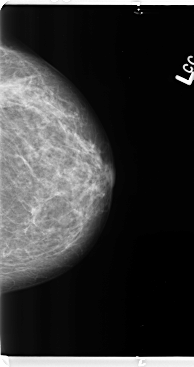

B_3145_1.LEFT_MLO

LEFT_MLO LINES 4744 PIXELS_PER_LINE 2720 BITS_PER_PIXEL 12 RESOLUTION 50 NON_OVERLAY